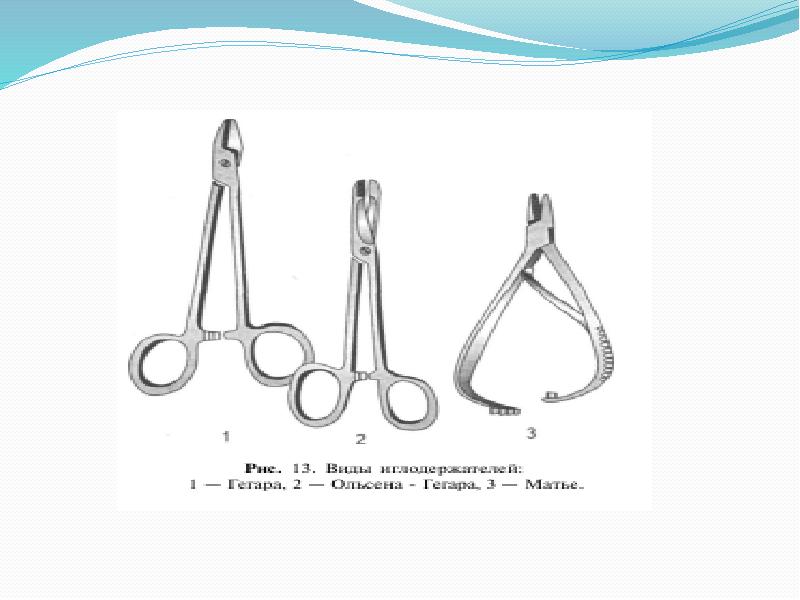

- 4. Иглодержатели Иглодержатель Гегара

- 5. Иглодержатель Матье Иглодержатель Матье

- 7. Иглодержатель Кастровьехо Иглодержатель Кастровьехо